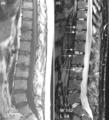

(a) T1-weighted and (b) short tau inversion recovery (STIR) magnetic resonance images of lumbar and lower thoracic spine in psoriatic arthritis. Signs of active inflammation are seen at several levels (arrows). In particular, anterior spondylitis is seen at level L1/L2 and an inflammatory Andersson lesion at the upper vertebral endplate of L3.